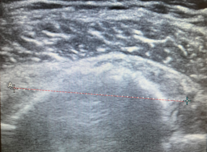

Ο ασθενής με ρήξη του στροφικού πετάλου του ώμου χρειάζεται εκτίμηση από εξειδικευμένο Ορθοπαιδικό Χειρουργό. Ο κ. Βλάχος αφού λάβει το ιστορικό σας και σας εξετάσει πολύ προσεκτικά, θα πραγματοποιήσει υπερηχογράφημα με σκοπό να ελέγξει την ακεραιότητα των τενόντων του στροφικού πετάλου. Επίσης θα χρειαστεί η λήψη μιας ακτινογραφίας ώστε να αποκλειστεί το ενδεχόμενο οστεοαρθρίτιδας ή άλλων παθήσεων του ώμου. Σε συγκεκριμένες περιπτώσεις ο ιατρός θα χρειαστεί να σας παραπέμψει για μαγνητική τομογραφία του ώμου με σκοπό την αξιολόγηση της θέσης και του μεγέθους της ρήξης, καθώς και τυχόν ατροφίας των μυών.